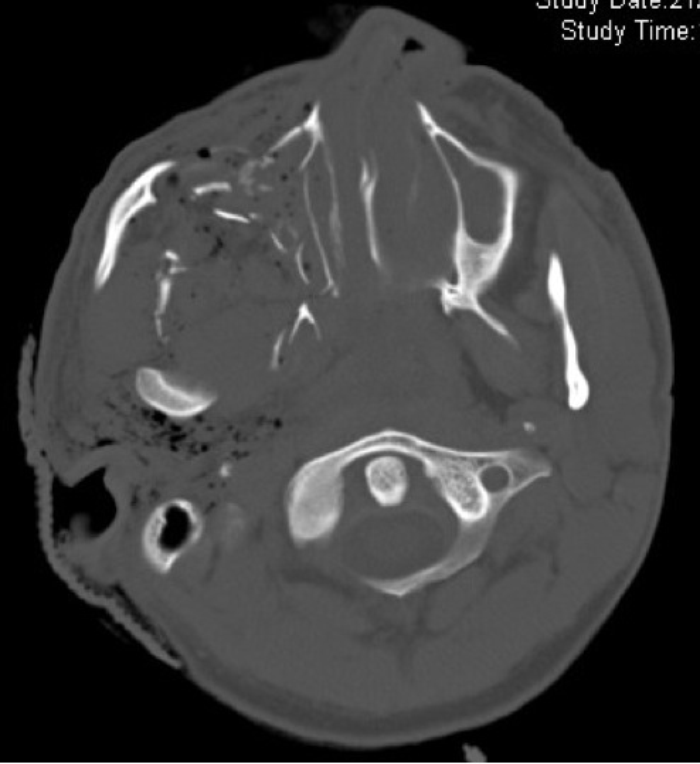

Figure 3: Axial CT scan illustrating a penetrating injury involving the maxilla and temporal bone.

Extensive soft tissue injury, typical of penetrating trauma, below the skull base and associated surgical emphysema is seen.